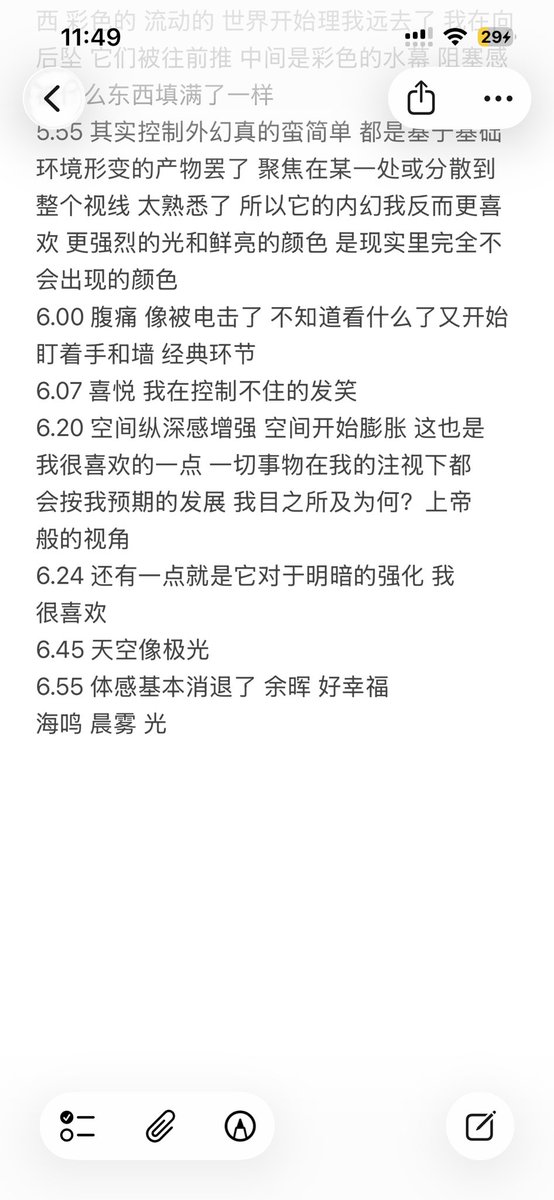

今天起来特别晕,完全不知道是怎么回事,以为是昨天测试物质的副作用我在想这么恐怖,然后怀疑今天是不是丁螺环酮吃了两次,直到我去看用药记录。。

好家伙唑吡坦又骗我吃药了还顺带上了个失忆状态,这下子知道是谁干的了。吃auv之后dxm清除得特别慢...让我感觉要从此告别了的程度,加上我基因检测本来cyp2d6就是中速代谢,这个尾巴就被拖的特别长